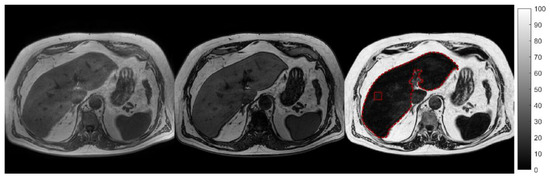

2.2. Liver Fat Content

2.2.2. MRI

2.3.2. Volumetric Analysis of Liver Fat